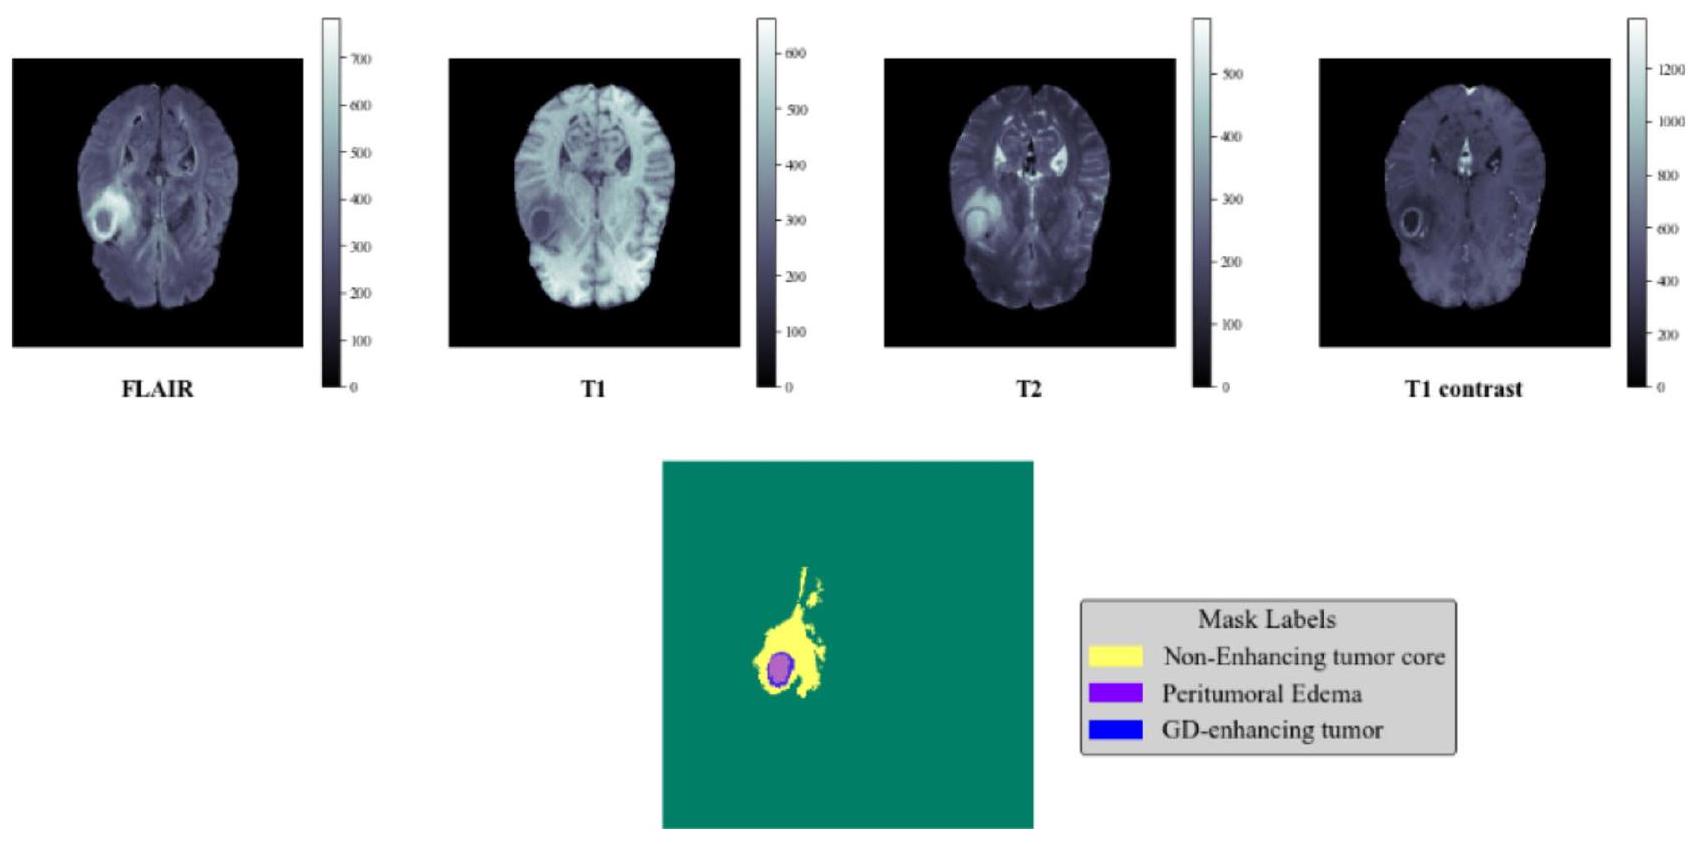

تستخدم هذه الدراسة مجموعة متنوعة من أنماط التصوير بالرنين المغناطيسي (MRI)، بما في ذلك التصوير بالرنين المغناطيسي المعتمد على استعادة الانعكاس السائل، والتصوير بالرنين المغناطيسي المعتمد على كثافة البروتون، والتصوير بالرنين المغناطيسي المعتمد على T2، والتصوير بالرنين المغناطيسي المعتمد على T1، لتحديد أورام الدماغ. يعتمد العلاج الفعال لأورام الدماغ على الكشف المبكر. يتطلب الأمر دراسة إشعاعية عندما يكون هناك اشتباه سريري في وجود ورم دماغي لتحديد الموقع الدقيق، ومدى التأثير على المناطق المجاورة. بناءً على هذه المعلومات، يمكن تحديد العلاج الأنسب، سواء كان جراحة، أو علاج إشعاعي، أو علاج كيميائي. يمكن أن يزيد الكشف المبكر عن الورم بشكل كبير من فرص بقاء المريض. يوضح الشكل 2 التصور لفحص الرنين المغناطيسي متعدد الأنماط للدماغ.

الشكل 2. تصور لفحص متعدد الأنماط لتصوير الرنين المغناطيسي للدماغ.

في هذا البحث، نقيم فعالية طريقة استخراج الميزات والتقسيم المقترحة باستخدام مجموعة بيانات BraTS2020، التي تتكون من 368 مسحة رنين مغناطيسي للدماغ مع تسميات، كل منها بحجم مع 155 شريحة، واستخدام واحدة من أربع أوضاع تصوير، وهي T1 وT1C وT2 وFLAIR، كما هو موضح في الشكل 4. تم إجراء التجربة على جهاز مزود بمعالج i7-6500U يعمل بسرعة من ذاكرة الوصول العشوائي، وNVIDIA GEFORCE GTX. توفر كل وضع تصوير معلومات فريدة لتحديد أورام الدماغ، مثل أنه يمكن تحديد الأنسجة السليمة في صور T1، ويمكن تحديد حدود الورم باستخدام وضع T1C، ويمكن تمييز مناطق الوذمة من السائل الدماغي الشوكي في صور FLAIR، وتكون صور T2 مفيدة لتحديد مناطق ورم الوذمة. جميع أوضاع التصوير مدرجة في طريقتنا المقترحة ومعالجة مسبقًا قبل استخدامها كصور إدخال للشبكات العصبية.

الشكل 4. تصور أوضاع التصوير: T1C (T1-weighted المعزز بالتباين)، T1 (T1-weighted)، FLAIR (استعادة التخفيف السائل)، T2 (T2-weighted).